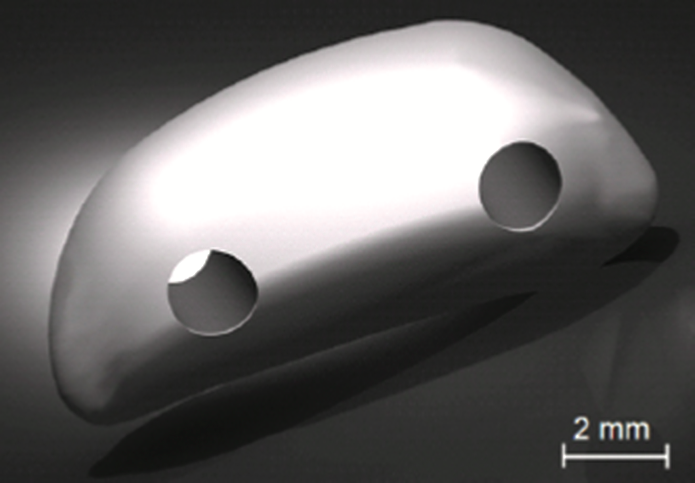

3D printed implant.

OIC built an artificial patella using FDM® technology, an additive manufacturing process that builds plastic parts layer-by-layer from CAD files, on its Stratasys® 3D printer using PC-ISO™ biocompatible polycarbonate (ISO 10993 USP Class VI). Physical testing was performed on the implant to validate its ability to provide the necessary mechanical strength. The implant was sterilized using ethylene oxide at 54°C (130°F) for one hour. During Oreo’s surgery, the implant was attached to the tendon and quadriceps using polypropylene sutures.

FDM printed patella pictured before implantation.